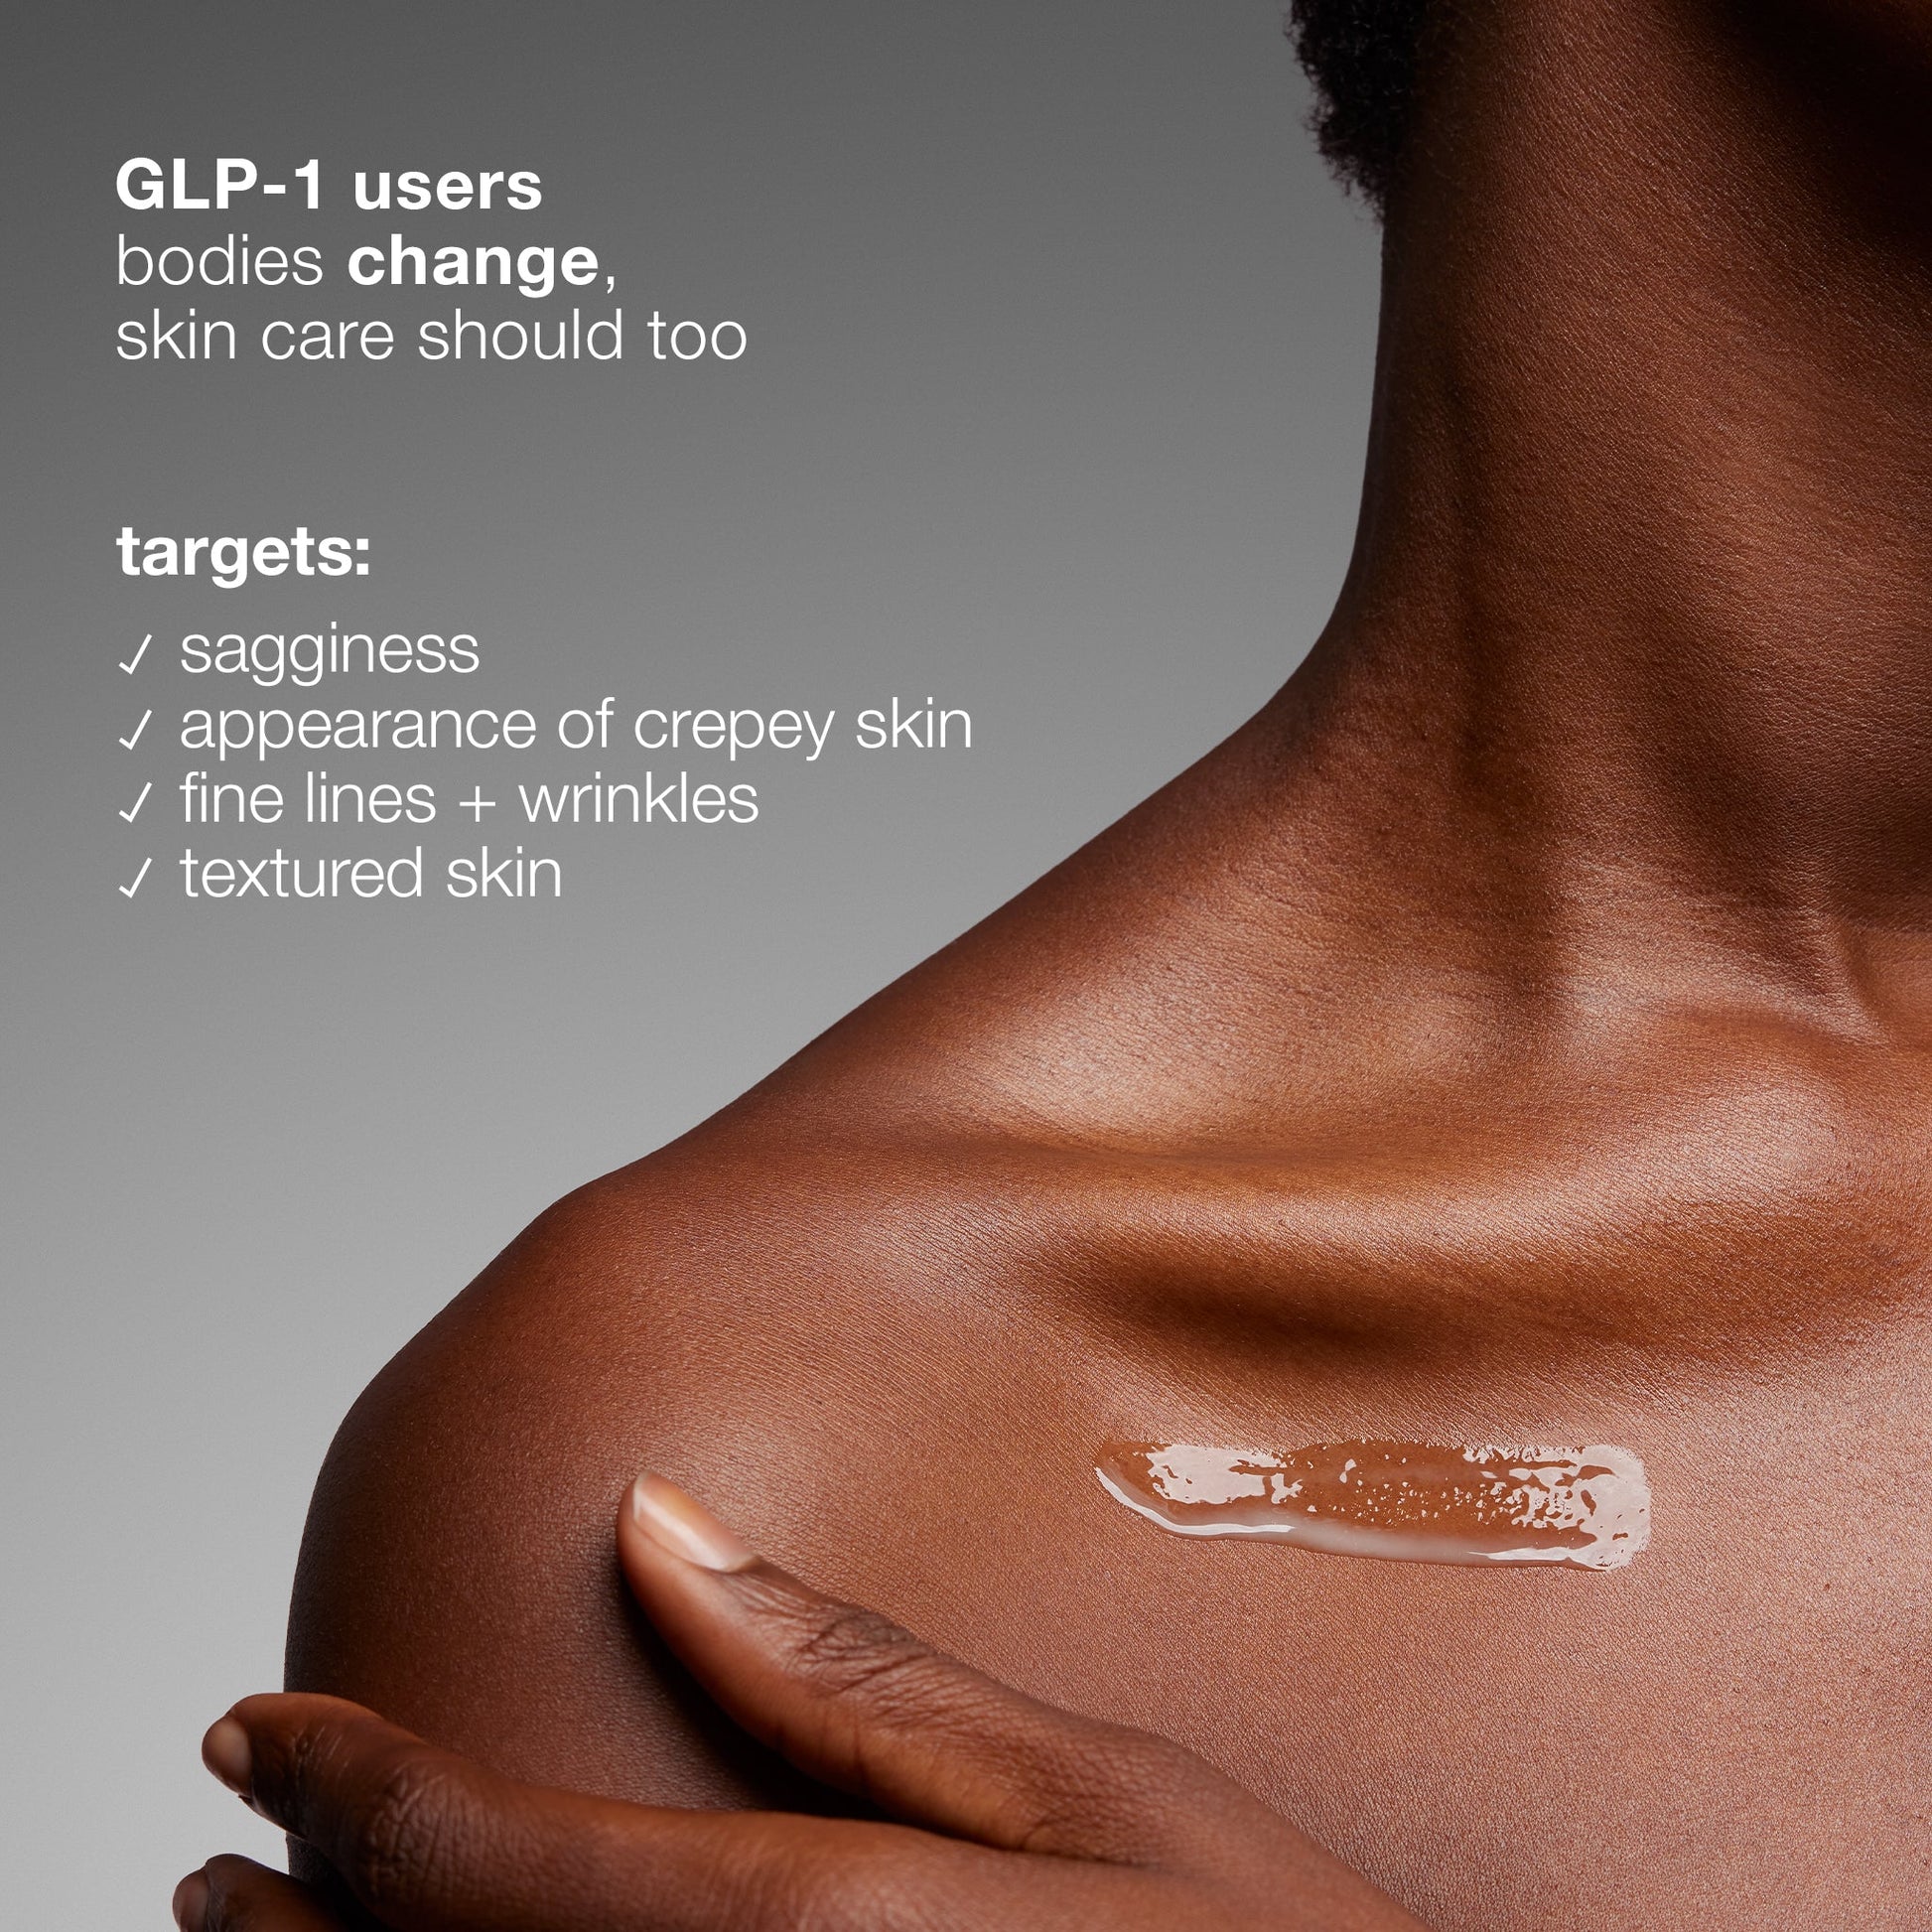

recommended for:

- sagging

- crepiness

- rough texture

- dehydration

- GLP-1 users

recommended for:

- sagging

- crepiness

- rough texture

- dehydration

- GLP-1 users